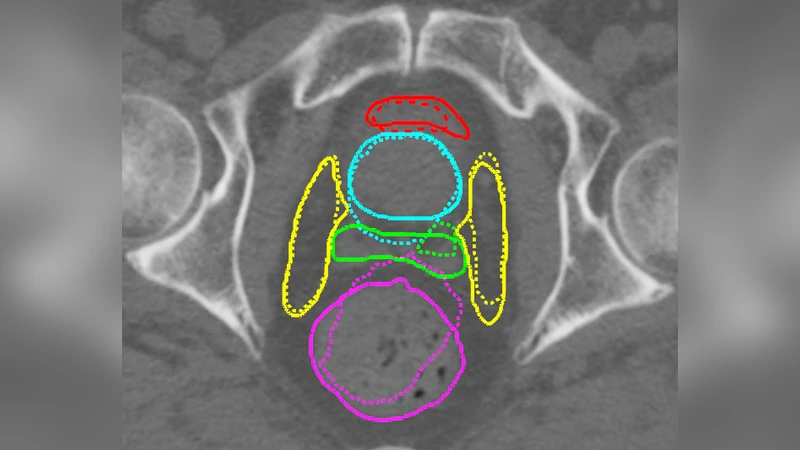

본 연구는 고정 영상과 이동 영상, 그리고 두 영상의 라벨을 학습 단계에서만 이용하고 테스트 단계에서는 라벨 없이도 3차원 변형 벡터 필드(DVF)를 추정하는 적대적 신경망을 제안한다. 생성기(Generator)는 DVF를 예측하고, 판별기(Discriminator)는 정합된 영상과 라벨의 일치를 평가한다. 프로스테이트 CT 데이터셋에 적용한 결과, 전통적인 elastix 기반 정합보다 평균 표면 거리와 95% Hausdorhaus 거리 모두에서 유의하게 개선되었으며, 실행 시간은 0.6초로 실시간 적용이 가능함을 보였다.

3. 판별기 설계: PatchGAN을 차용해 입력을 (I_f, I_m(Φ), S_m(Φ)) 형태의 3채널 텐서로 구성한다. 두 가지 변형을 실험했는데, 하나는 라벨을 별도 채널로 입력하고(JRS‑GAN a), 다른 하나는 라벨을 이미지와 곱해 구조적 강조를 유도한다(JRS‑GAN b). 판별기는 지역적인 정합 품질을 스칼라가 아닌 패치 단위로 평가함으로써 미세한 변형 오류도 감지한다.

6. 데이터 및 평가: 18명의 전립선 암 환자(각 7~10회 반복 CT)에서 111개의 학습/검증 쌍과 50개의 테스트 쌍을 구성했다. 평가 지표는 평균 표면 거리(MSD)와 95% Hausdorff 거리(HD)이며, 통계적 유의성 검증을 위해 Wilcoxon signed‑rank test(p = 0.05)를 사용했다.

7. 실험 결과: 모든 비교군(elastix‑NCC, elastix‑MI, Reg‑CNN, JRS‑CNN, Reg‑GAN)보다 JRS‑GAN a/b가 MSD와 HD 모두에서 유의하게 낮은 값을 기록했다. 특히 방광·직장 등 위험 기관의 HD 감소가 두드러졌다. Jacobian determinant의 표준편차는 elastix‑MI(0.08)보다 JRS‑GAN a(0.17)에서 더 큰 변형 다양성을 보였지만, 이는 정합 정확도 향상과 상충되지 않는다. 실행 시간은 GPU(V100) 기준 0.6 초로, CPU 기반 elastix(13 초) 대비 20배 이상 빠르다.